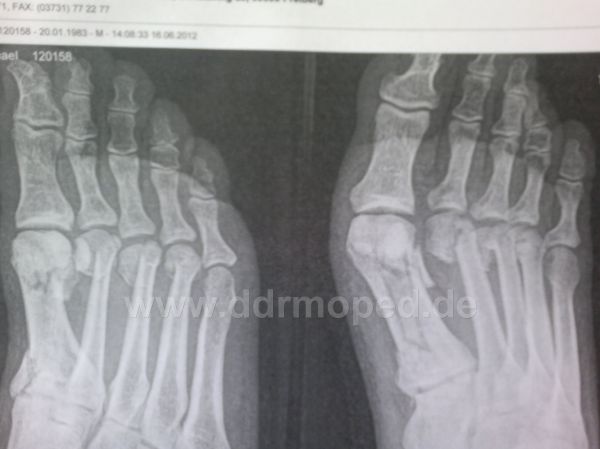

| QUOTE (Neumi83 @ 16.06.2012, 16:24) | | Hatte heute nen kleinen Rennunfall beim 12h Rennen |

Hallo Micha, na dann gute Besserung von mir! Jürgen

Micha, auch von mir alles Gute für die Genesung!!! Auf dass du und der Essi bald auf die Beine kommen... Glück im Unglück, da hast du ja nun bissel viel Zeit und kannst dich mit PS7 intensiv beschäftigen.  Wann soll ich liefern? Grüsse von uns Beiden

Mensch Micha, alles Gute und gute Besserung!!! Nils